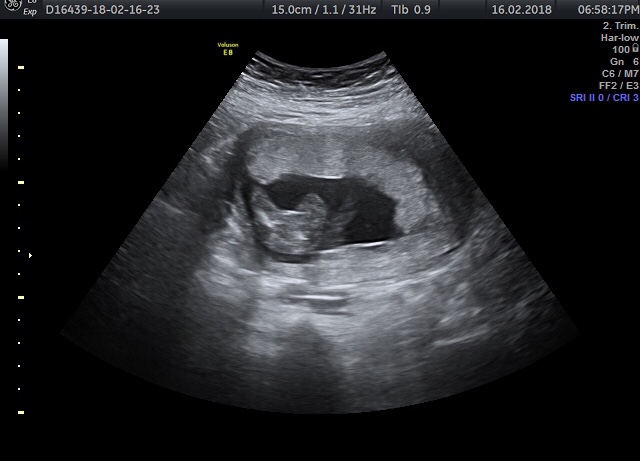

I was told girl again (after being told at 16w) saw lines in the scan but on the pics I was given there are no magic 3 lines 🙄 would you be happy to say girl or wait and try again on another scan?!Attachment 38836Attachment 38837Attachment 38838

That's a girl!

I've seen many boys in my day and that is definitely a girl

totally girl!!

A girl! Congratulations!

That looks like a girl to me!